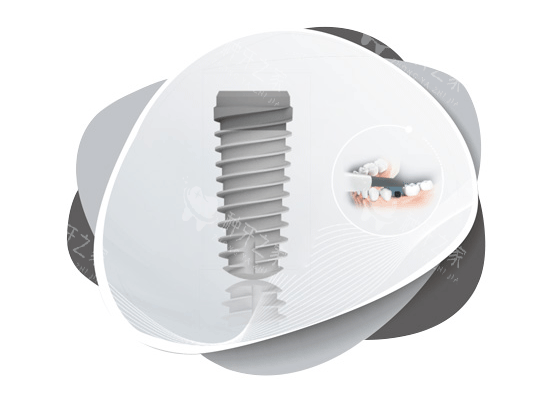

接着是植入种植体,恰似用钢筋水泥浇筑地基。在局麻或静脉麻醉下,医生将钛合金种植体比较准植入牙槽骨,如同 “埋入地基钢筋”。部分机构会采用 AI 动态导航技术,避开神经血管,误差小于 0.1 毫米。若骨条件良好,拔牙后可立即植入种植体,缩短治疗周期。植入后,医生会对仅 3 - 5 毫米的切口进行缝合,术后 1 - 2 周拆线。